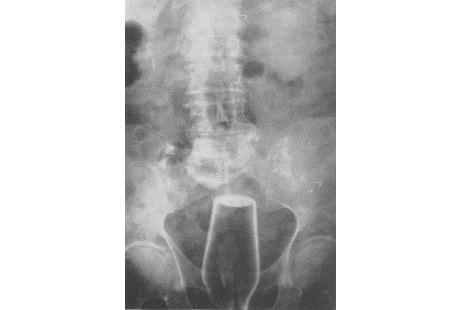

Saat ia sedang asyik-asyiknya jongkok, toilet umum dari bilik kayu sederhana itu jebol dan ia terjatuh dalam posisi terduduk. Tampaknya ketika terjatuh itu, tubuh si kakek menimpa sebuah botol kosong dan tahu-tahu botol itu tadi masuk ke lubang anus si kakek.

Dari hasil pengamatan dokter, sepertinya leher botol tersebut retak di dalam tubuh si kakek sehingga ia merasakan nyeri yang luar biasa. Botol itu ditemukan di usus bawah si pasien dengan posisi leher di sekitaran anus.